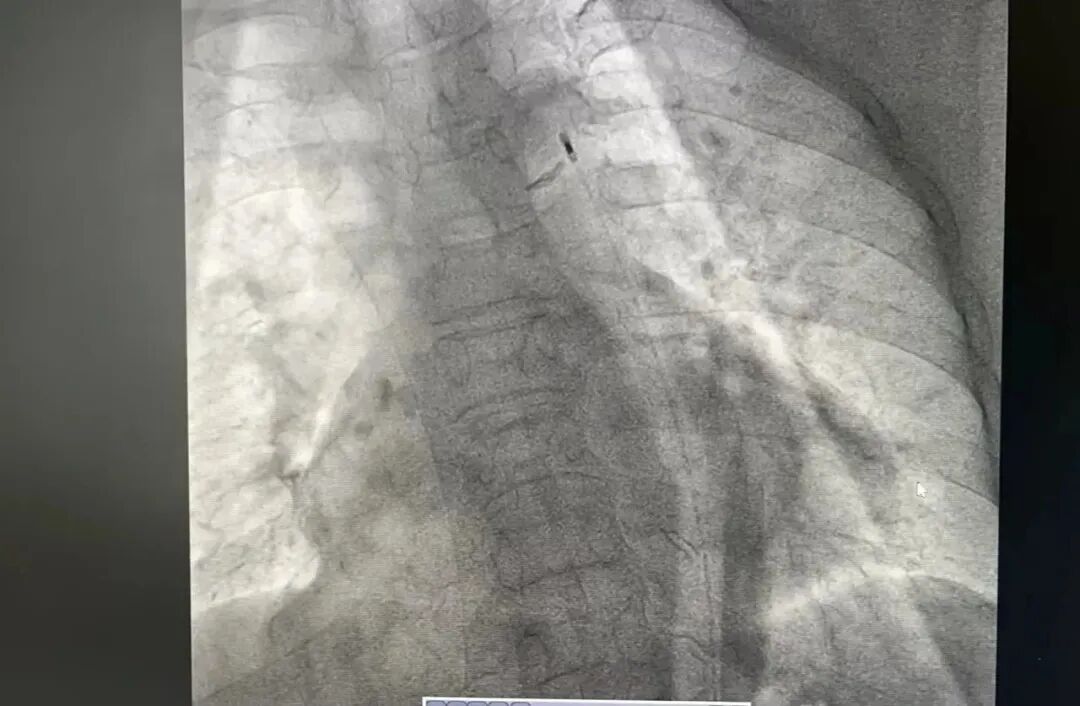

“让一让,病人要立即抢救”,一名老年女性患者正躺在推车上,向心内科导管室飞奔而去。患者持续胸痛,危重症急性心肌梗死,需要立即抢救。此时,心内科主任医师漆军华、主治医师张敦福已经在手术室等待。 漆军华了解到,患者有高血压及劳力性胸痛20多年,3天前起反复胸痛,此次因胸痛持续就诊,结合心电图判断,患者很可能冠脉病变复杂,遂立即向心内科主任陈立娟汇报病情,陈立娟主任指示立即行冠脉造影。 果不其然,冠脉造影结果显示严重三支病变,左主干疑似夹层,左前降支全程严重钙化纤细伴重度狭窄,左回旋支开口狭窄95%以上,可见左冠向右冠提供侧枝循环,右冠状动脉巨大,全程严重钙化,中段完全闭塞,且患者持续胸痛不缓解,血压偏低,基本可以判定患者病情危重,随时有生命危险。 陈立娟仔细查看造影影像后,判断立即行血运重建是拯救患者生命的唯一出路,溧水区人民医院导管室有抢救危重患者的利器——主动脉球囊反博(IABP),建议在主动脉球囊反博(IABP)支持下进行手术。 得到家属同意后,值班护士张燕萍、周红迅速启动IABP机器,配好抢救药品,陈立娟与漆军华穿上铅衣准备上台。看着严阵以待的心内科团队,家属对医院充满了信赖。 手术准备就绪,陈立娟和漆军华迅速穿刺股动脉,送入IABP球囊,两位护士熟练地连接好主动脉球囊反博仪并打开机器,此时患者胸痛有所减轻。左指引导管到位后,工作导丝通过前降支病变送至远端,但因患者冠脉钙化严重,即使最小的球囊也无法通过病变。 面对困境,陈立娟果断改变思路,患者右冠巨大,供血范围极大,如果能开通右冠,有极大的可能性保住患者生命线,幸运的是,在微导管后支撑下,工作导丝很快就通过了中段闭塞病变,随后在右冠植入支架,支架植入后,患者胸痛明显缓解,生命危险终于解除。手术很成功,患者术后转中大医院继续治疗,目前恢复良好,已经出院。